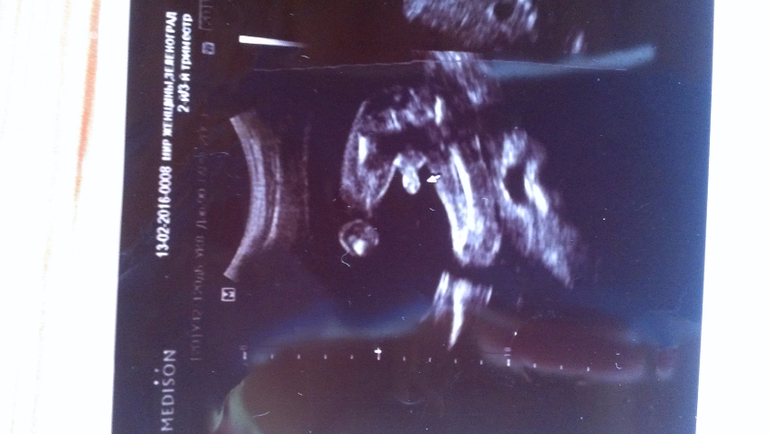

Внутриутробное развитие двойни/тройниНа узи в 20 недель уверенно сказали - два мальчика и на снимках так четко выделили, а неделю назад в другом центре врач как раз не очень уверенно, но предположила, что обе девочки...

На узи в 20 недель:

А у вас ну очень похожи на пацанов)

Вот мне тоже кажется, что, по крайней мере, с одним не могли ошибиться)) В любом случае, розовое (как и голубое) закупать не планировала, но люблю быть готовой.

Еще, все кто видел верхнее фото - сразу сказали, нос папин. Надеюсь, мальчику достался))